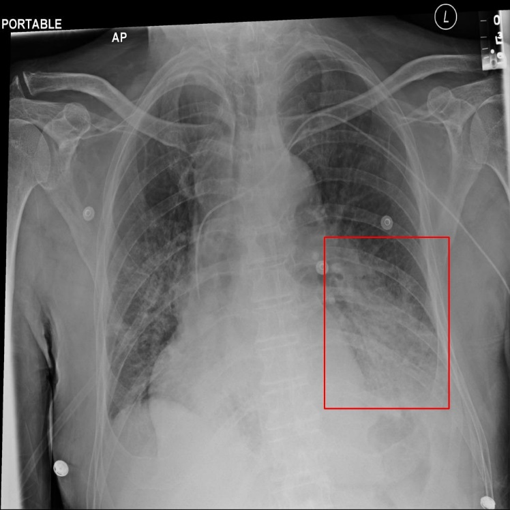

Figure 1: Examples of the five categories of X-ray images in the dataset, the first is a normal chest X-ray image without pneumonia, and the other four are images of four different types of pneumonia. The bounding boxes in the X-ray images are the area of the pneumonia lesions identified and marked by the doctor.

The dataset we employed consists of 20,012 X-ray images of pneumonia. As shown in Fig.1, there are five categories in the dataset, one category is normal X-ray images without pneumonia lesion, and the other four categories are X-ray images with different kinds of pneumonia. The pneumonia lesion areas of these four types of images are marked by highly-trained radiologists through bounding boxes, whose coordinates are available. We divided the pneumonia dataset into the training set and test set, and the rule of division is to randomly select 10% of images of each category to form the test set, and the remaining 90% is used as the training set. Each image is a single-channel chest X-ray with the resolution of 1024x1024. The dataset is available at https://god.yanxishe.com/23?from=god_home_list.